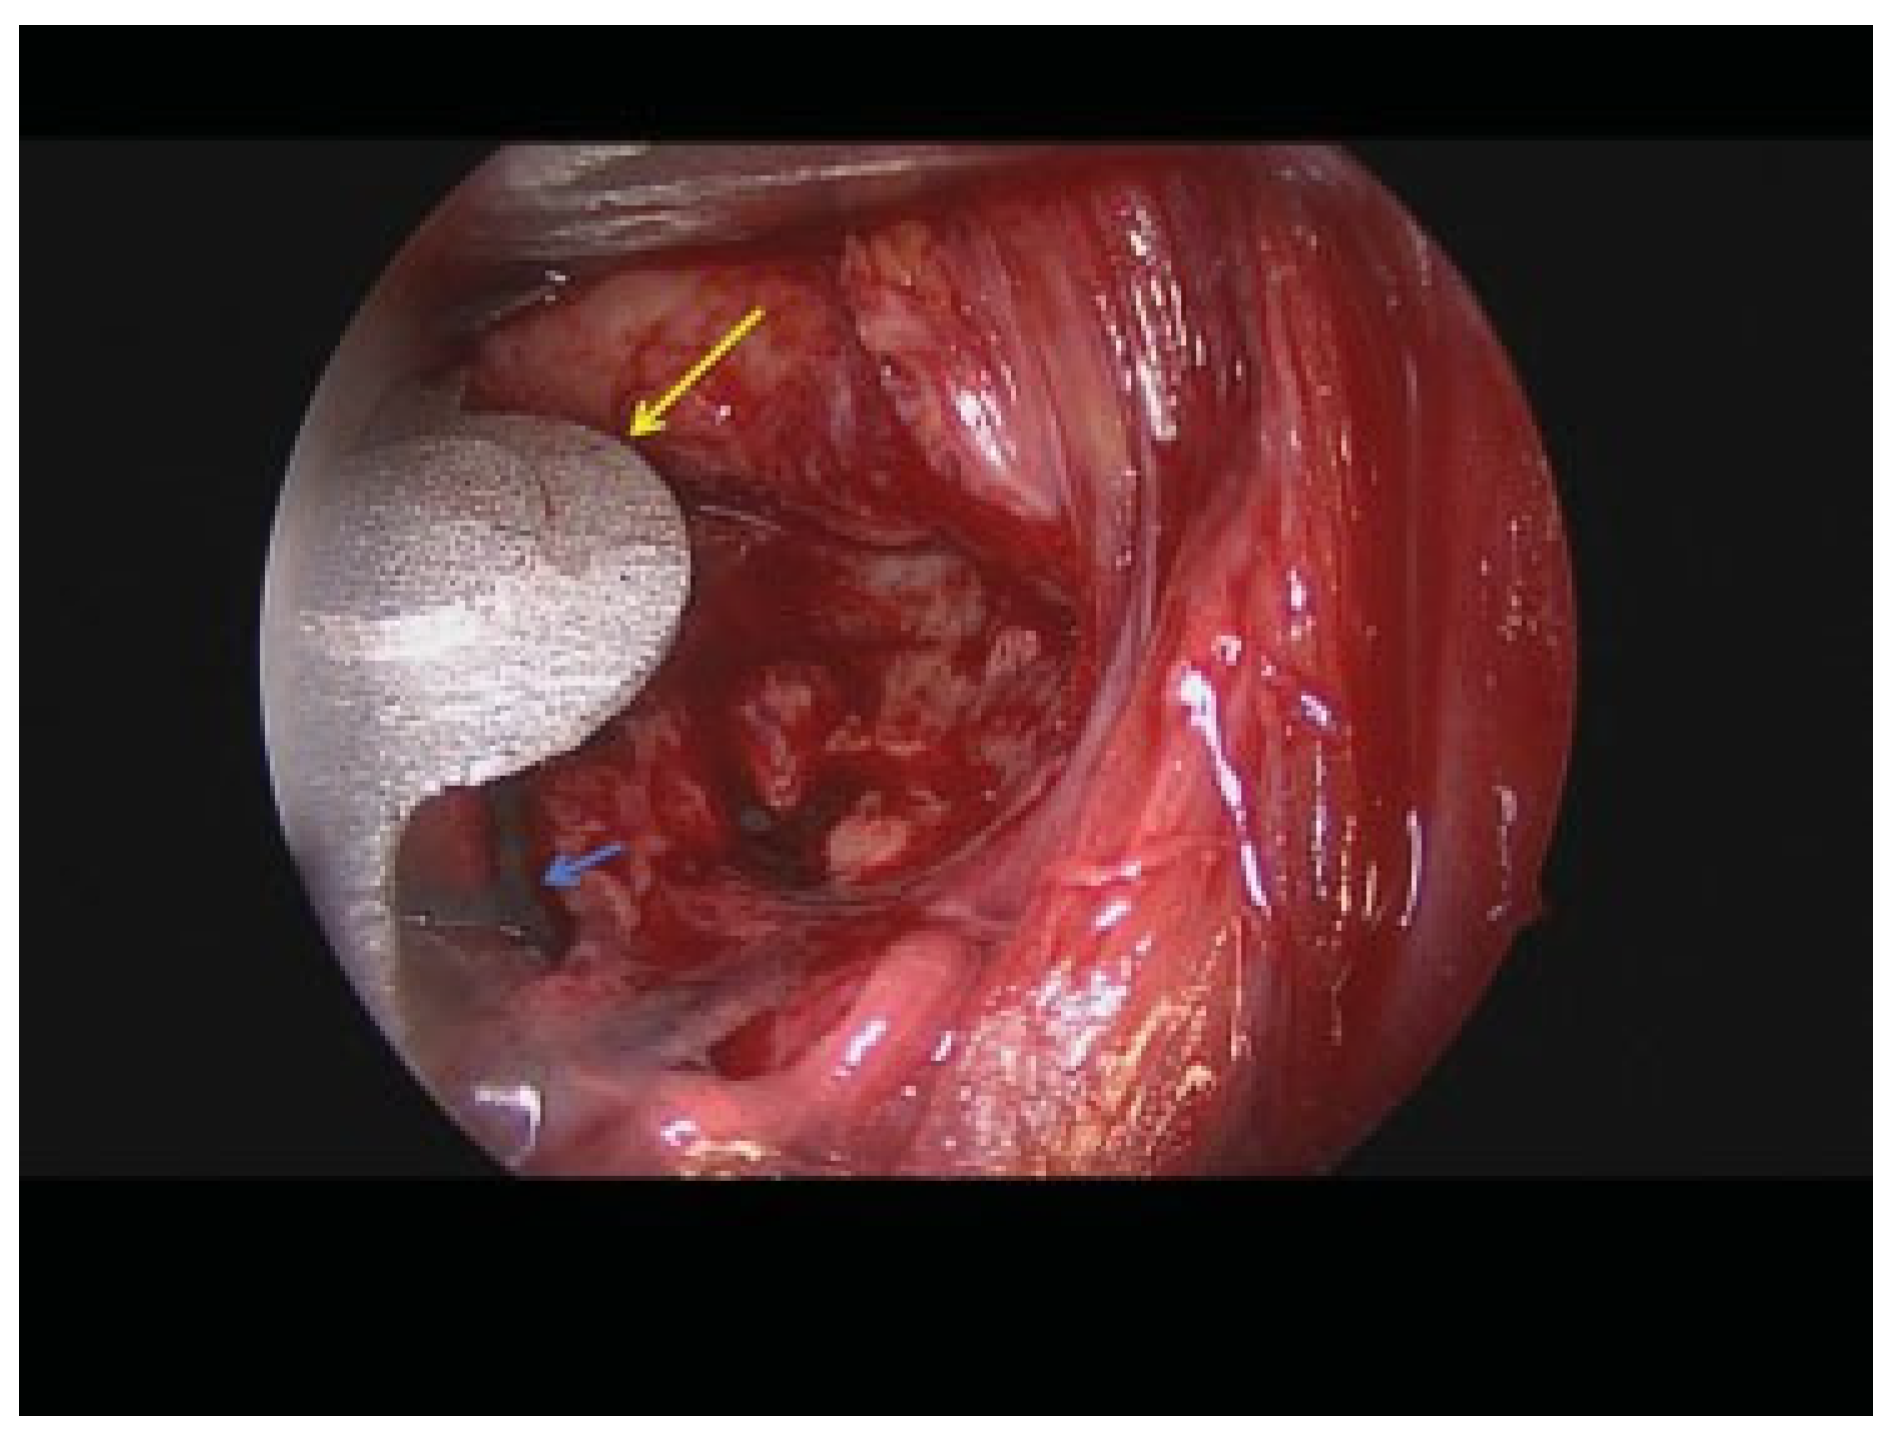

Figure 11. Case 3: Intraoperative endoscopic view of the lateral plate in situ (long yellow arrow) and the previously adapted titanium mesh (small blue arrow).